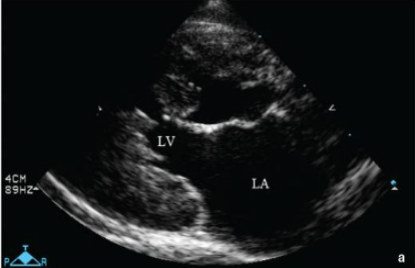

Khi mèo bị HCM nặng, siêu âm tim thường rõ ràng các dấu hiệu như: dày thành thất trái khu trú hoặc toàn bộ, cơ nhú phì đại nặng, hiện tượng SAM, mất khoang thất trái kỳ tâm thu, giãn nhĩ trái mức độ nhẹ đến nặng.

Giãn nhĩ MC 4 buồng cạnh ức phải

Dày thành thất trái kỳ tâm trương (a) và tâm thu (b)